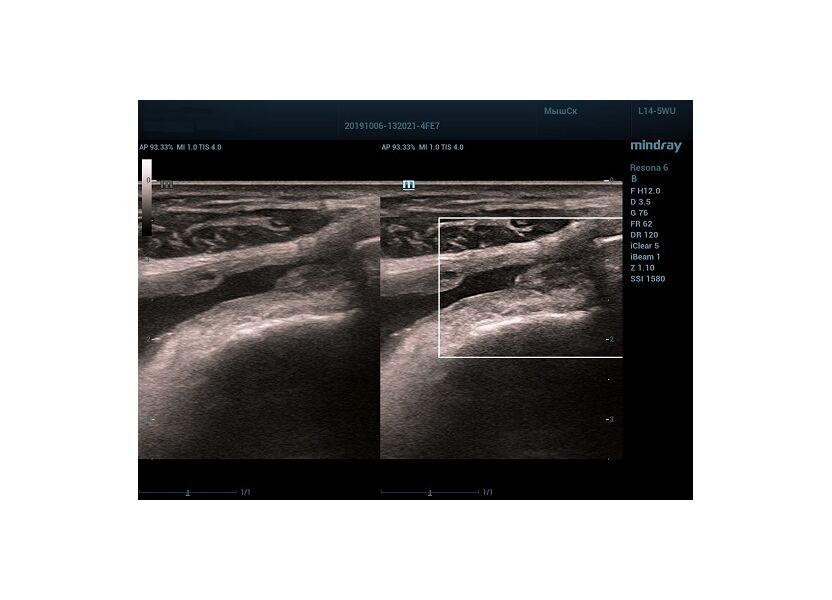

HD Scope позволяет достигать поразительной разрешающей способности выбранной зоны сканирования, при этом улучшая как детализацию, так и контрастность изображения. Помимо пространственного разрешения мы получаем преимущество и по разрешению во времени. Прибор получает огромное количество нативных изображений практически одновременно, и при сборе итоговой картины не происходит смещения объекта под датчиком, а значит и нет размывания изображения. Все участки раздела фаз, каждый контур образования теперь видны, мы все ближе к идеальной картинке.

Как он работает? Особенностью платформы ZST+, на которой построены приборы Mindray Resona, является так называемое многолучевое сканирование. В отличие от обычного датчика, который получает изображение в виде прямого эхо, датчики приборов этой серии проводят многолучевое сканирование каждым элементом с огромной скоростью, получая огромное количество данных. Затем происходит сложная постобработка и сбор из множества «многолучевых» снимков идеальной картинки.

Вторая особенность ультразвуковых машин данной линейки — это изменение расчетных констант распространения ультразвука, таким образом прибор перебирает для каждой ткани свои значения скоростей волны и пересчитывает каждую точку, делая менее выраженным поглощение по глубине. Эти особенности позволили использовать без фокусные технологии сканирования. Функция HD Scope позволяет использовать эти ресурсы для исследование небольшой области, значительно увеличивая качество изображения.